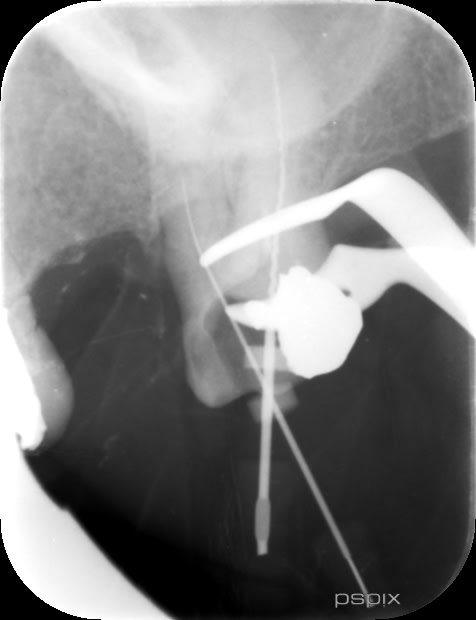

Voilà j'ai revu jeudi le patient, pour continuer la reprise de traitement.

J'ai mis en application vos conseils, et j'ai pu progresser. Mais.. je suis encore loin des apex.

- la racine MV : en passant le réciproc (que j'ai emprunté à mon collaborateur) j'ai pu progresser dans le canal sur quelques mm (j'étais étonné qu'à chaque rotation, je m'enfonçais d'un demi mm).

- la racine DV, j'étais bien sur une butée (Cf dent2660 ci dessus), et j'ai réussi à retrouver le chemin vers le canal en direction de l'apex.

- la racine P j'aimerai progresser de 2-3mm encore

Sur ces trois racines, mon reciproc tourne dans le vide et ne progresse plus. J'ai essayé de mettre de l'EDTA en gel (un produit qui s'appelle Canal+ ; j'ai également à disposition de l'EDTA 17% liquide en bouteille, si jamais vous pensez que c'est mieux).

Que préconisez vous pour la suite ?

Ci joint la radios pré et les radios per op. Les radios sont issues du pspix2, qualité pas folle.

Certains me disent que je perds mon temps, mais vu c'est une dent stratégique pour placer le futur stellite, j'aimerai la lui conserver.